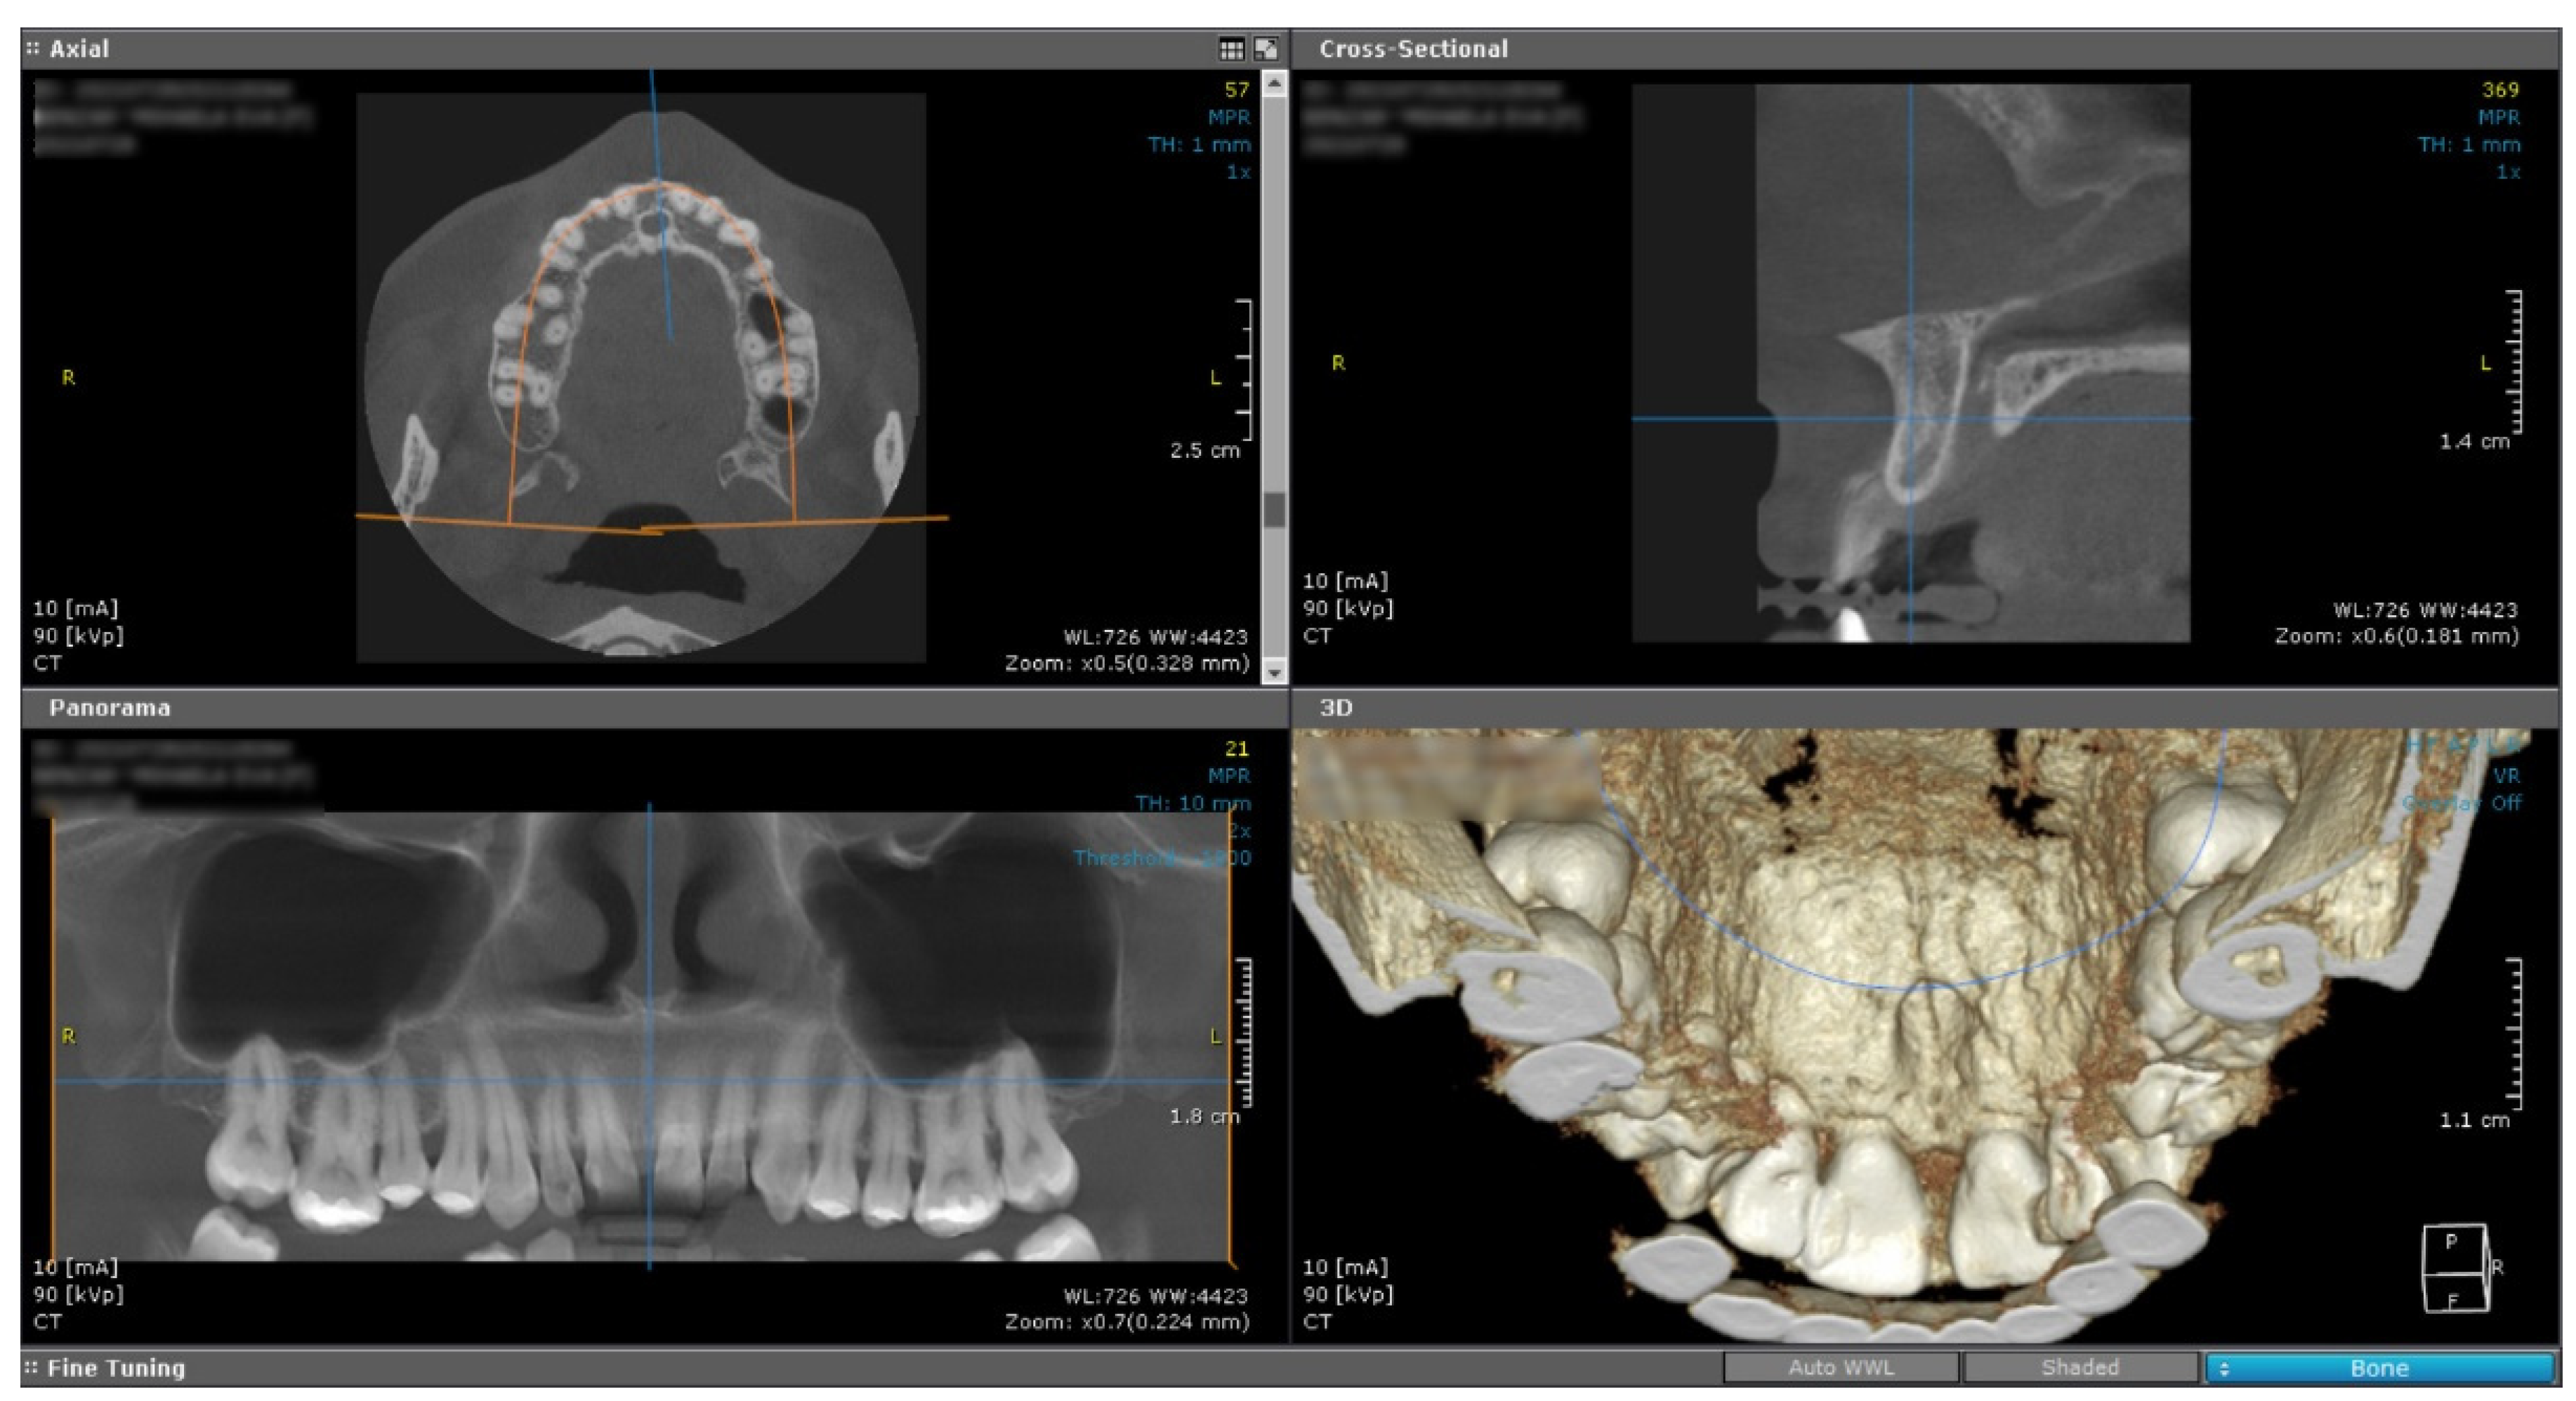

A cone beam computed tomography image (CBCT) did not reveal any changes of the subjacent bone structure in the anterior hard palate, suggesting the sole involvement of the soft tissue (Figure 2).

Figure 2. Cone beam computed tomography showed no underlying bone structure alteration.